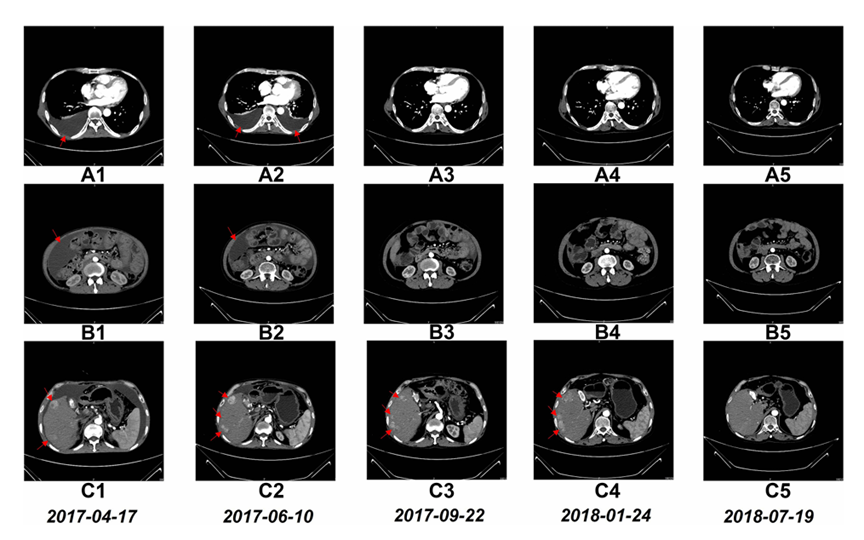

更令人惊喜的是CT扫描结果显示,NK细胞治疗后患者的胸水和腹水明显减少,肝叶中的多个肿瘤显著缩小。经过一年多的NK细胞治疗,这位患者的生存期已经成功超过了4年,有望突破五年生存大关!

图:NK细胞治疗前和治疗期间的CT扫描结果:经过6个疗程的治疗后,胸腔积液完全消失(A1至A5)、腹水几乎完全消失(B1至B5),经过17个疗程的治疗后,肝脏右叶的多个肿瘤大小显著减小(C1至C5)

图源:OncoTargets and Therapy